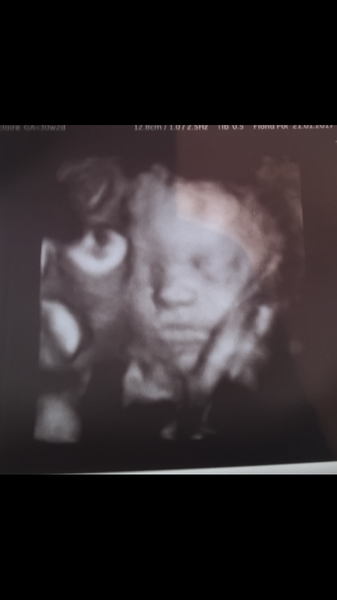

I have bubs 4d scan tomorrow at 30/2. Kinda excited seeing her again but also ahhhhhh at alien baby 😂😂

All good with 4d scan. Bubs looks adorable. Can't wait to meet her.

30.2w and weighs 3lbs 8oz 💓👶🏼💓

Def less alien like then 16w

blondes that's a gorgeous photo!

Blondes Lovely photo. Very sweet.

Blondes: great photo! A nice reminder that you're in the last part of the relay and the lovely prize at the end.

Blondes - that's a lovely scan photo!

Blondes - gorgeous pic! Not long now till you can squish those cheeks yourself.